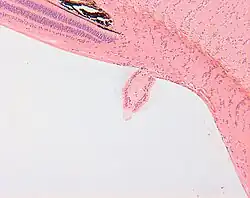

Bergmeister's papilla

Bergmeister's papilla arises from the centre of the optic disc, consists of a small tuft of fibrous tissue and represents a remnant of the fetal hyaloid artery.

The hyaloid artery provides nutrition to the lens during development in the fetus, and runs forward to the lens from the optic disc.[1] The optic disc is covered by a plaque of fibrous cells called the central supporting tissue meniscus of Kuhnt. This plaque forms a fibrous sheath around the hyaloid artery where it leaves the optic disc. At birth the hyaloid artery regresses, and is normally completely regressed by the time of eyelid opening. Bergmeister's papilla is a remnant of the hyaloid artery fibrous sheath and is frequently observed as an incidental clinical finding.[2] Bergmeister's papilla is named after Austrian ophthalmologist O. Bergmeister (1845–1918).